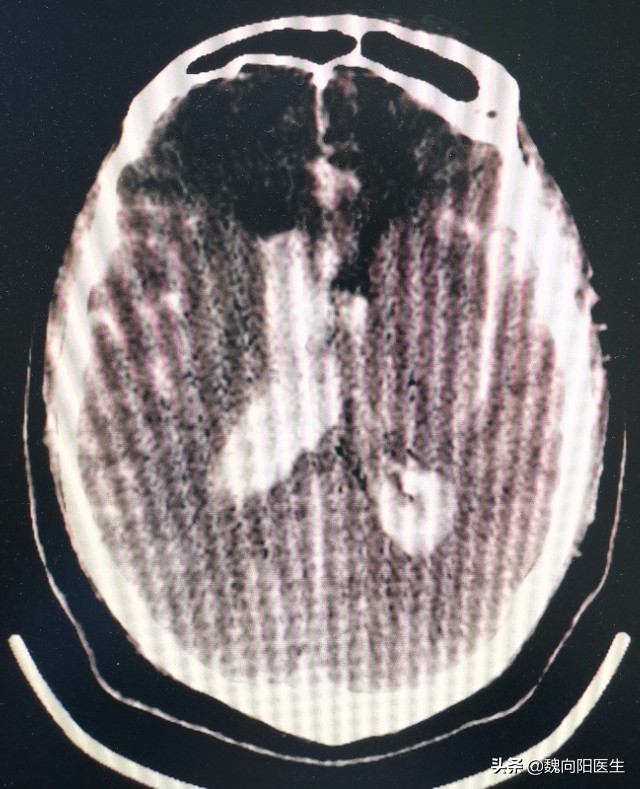

患者,男性36岁,今年对他来说可能就是本命年,一次“活动”之后突然就昏迷了。即送至当地医院,头CT说:“你脑出血了”。

医生当时就在脑袋上打了两个洞,放了两根管子进入脑室内,持续的引流颅内的血。

头上的管子放了一周多,血是太多了,实在不敢再放了(管子放的时间越长,颅内感染的风险越高)。且颅内的血液明显减少。